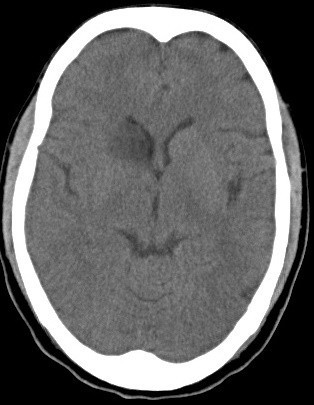

Image on left is SWI

Image on right is DWI